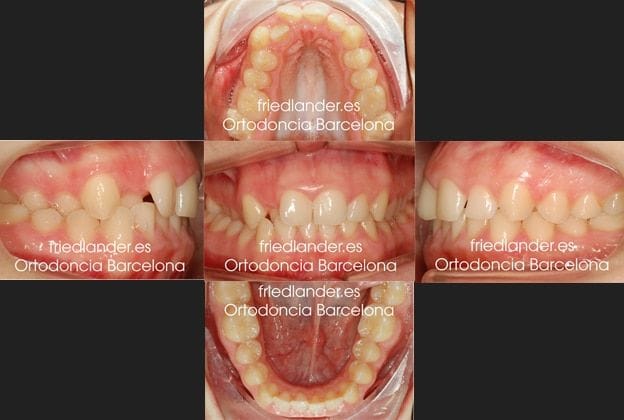

Al hacer la exploración observamos una mordida cruzada en el lado derecho de la paciente, un frente anterior con apiñamiento y un incisivo lateral que se encuentra por palatino. La línea media superior estaba ligeramente desviada y no coincidía con la inferior.